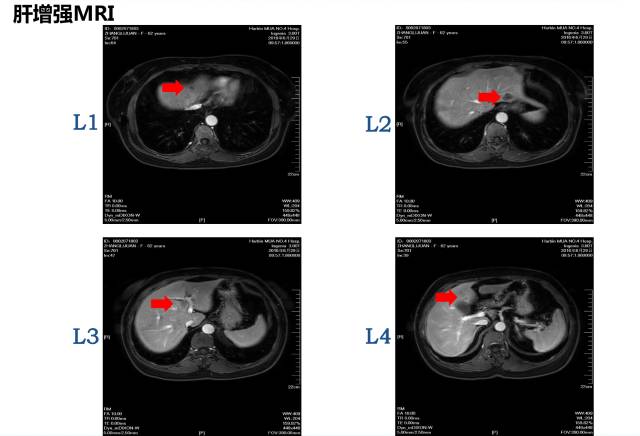

病理:盲肠腺癌肝脏MRI:共8枚病灶

邢宝才教授:1cm以上的病灶影像学特征较为明显,1cm以下的不明显病灶可以进行超声造影,CT敏感性约为80%,核磁共振(MRI)敏感性约90%多,核磁共振(MRI)+ 普美显敏感性约96~97%。针对小病灶,核磁+普美显的肝胆特异期联合DWI的检测误差较小。术前我们对病灶应进行细致的影像学评估,而判断是否转移应以术后病理结果为准。